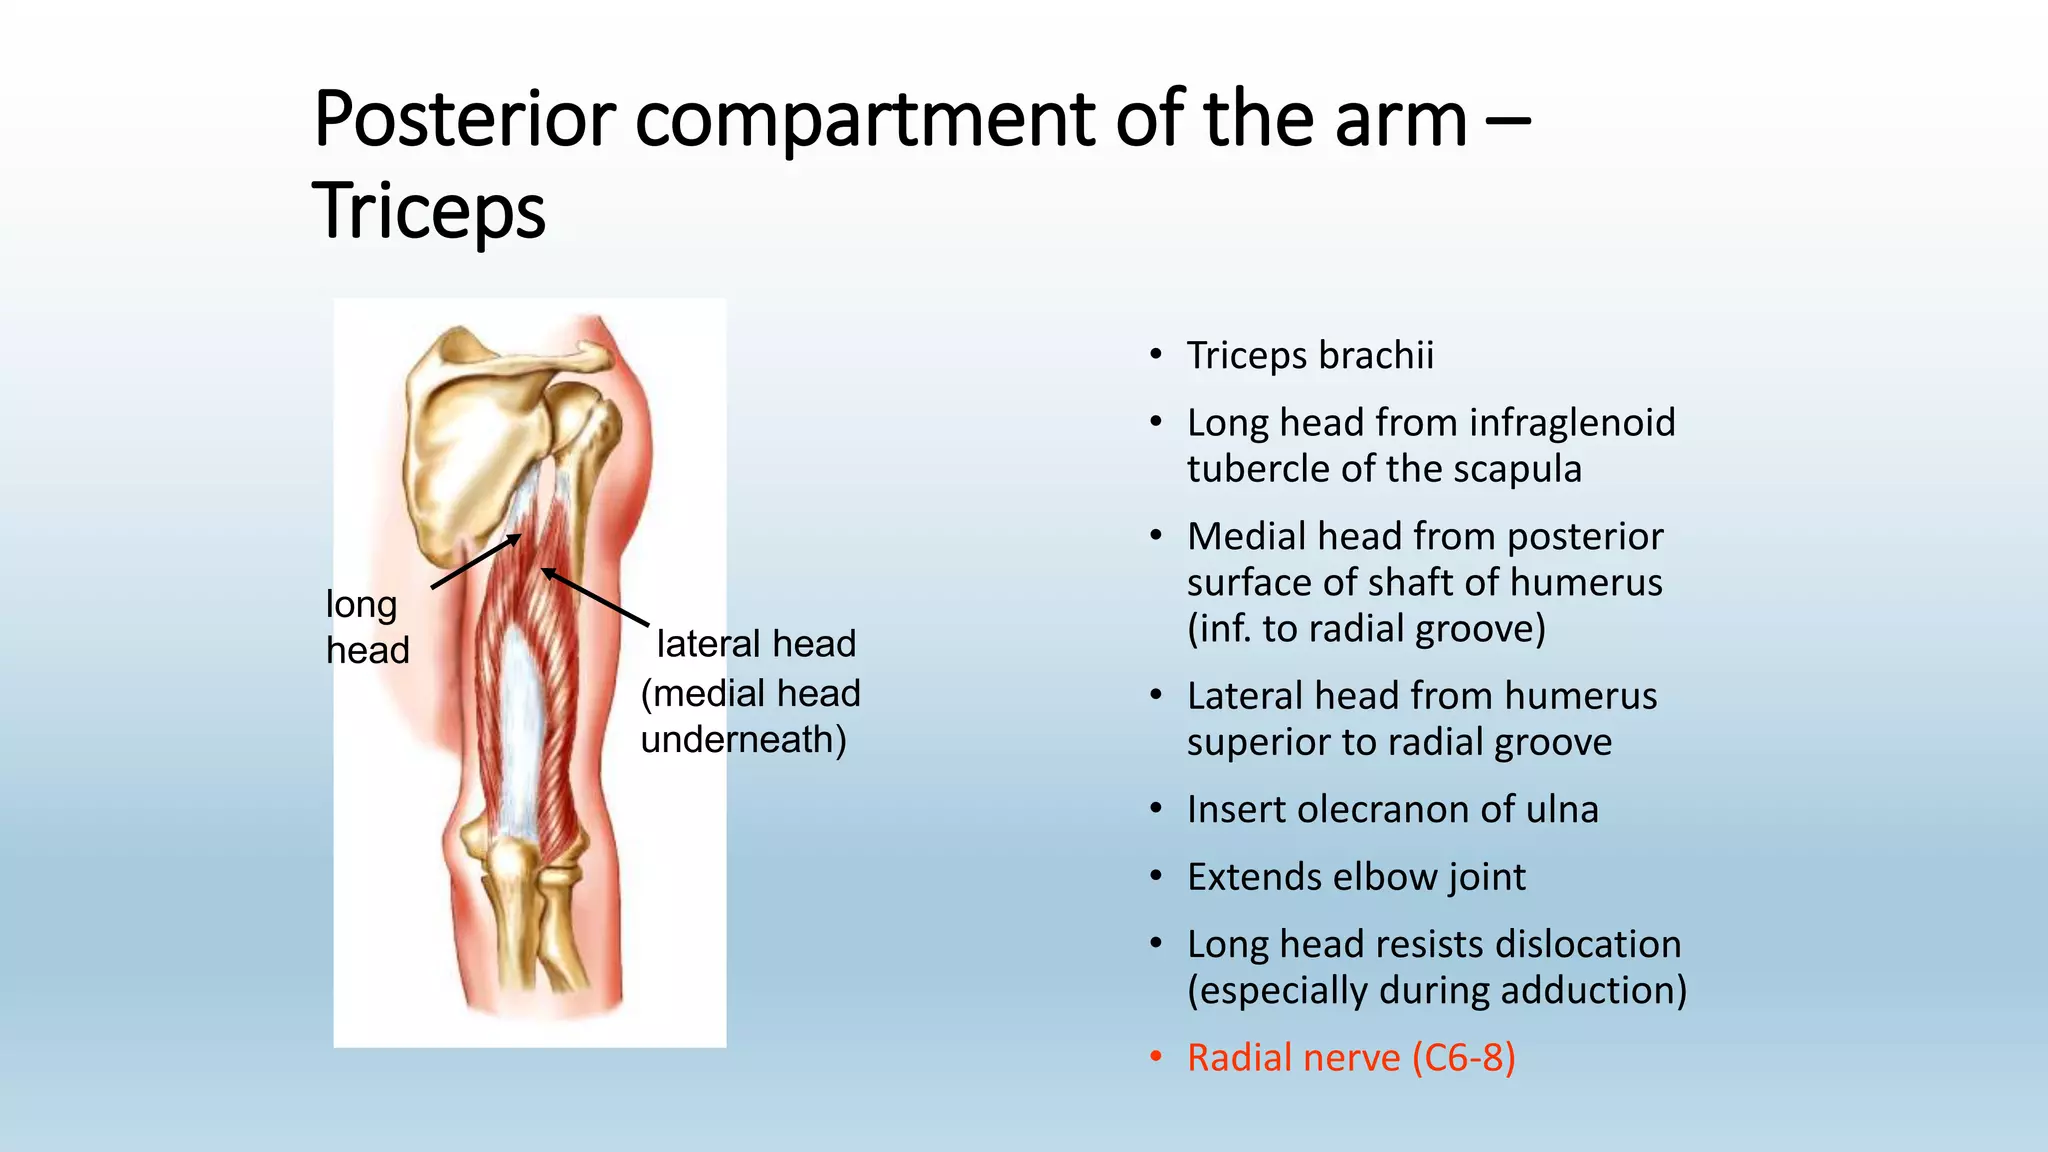

The document summarizes an anatomy revision session on the upper limb. It discusses various muscles of the upper limb including their origins, insertions, innervations and functions. Key muscles covered include the pectoralis major and minor, serratus anterior, deltoid, biceps brachii, brachialis, coracobrachialis, and triceps. It also discusses the rotator cuff muscles and muscles of the forearm including flexor carpi ulnaris and radialis. The session aims to help students identify upper limb muscles and understand their relations to nerves.